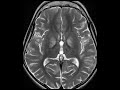

Mitochondrial Deletion

These images demonstrate T2 FLAIR hyperintensity within the bilateral globus pallidus, thalami, periventricular white matter, midbrain, and dorsal pons. In addition there are areas of subcortical and periventricular white matter T2 FLAIR hyperintensity. Many of these foci demonstrate restricted diffusion compatible with ischemia. This patient has a history of mitochondrial DNA deletion syndrome and presented with worsening ataxia. Findings for mitochondrial deletions generally involve the bilateral deep gray matter and peripheral white matter as seen here. If spectroscopy is performed, you would expect to find elevated lactate levels.